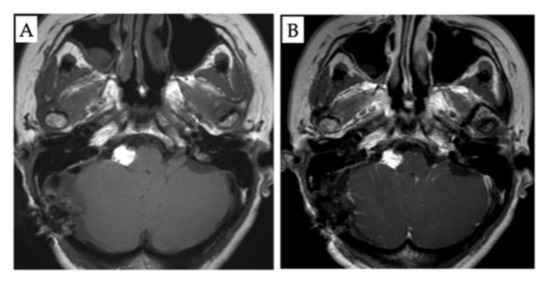

2. Case Presentation